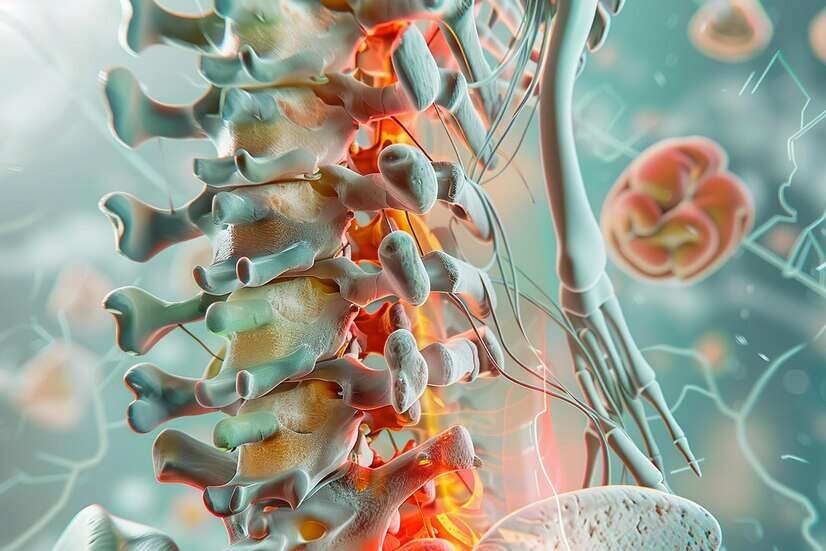

Spine surgery is a medical intervention aimed at relieving spinal disorders, restoring function, and alleviating pain. Indications for spine surgery include herniated discs, spinal stenosis, scoliosis, spinal fractures, tumors, and degenerative conditions. Surgical options vary depending on the condition and may involve discectomy, laminectomy, spinal fusion, artificial disc replacement, or minimally invasive procedures. The goals of spine surgery are to relieve pressure on spinal nerves, stabilize the spine, improve mobility, and reduce pain. Patients should expect thorough pre-operative evaluation, discussion of risks and benefits, and post-operative care involving pain management, physical therapy, and follow-up appointments. Advances in technology, such as navigation systems and robotic-assisted surgery, enhance precision and reduce recovery time.

Patients should discuss their specific condition, treatment options, and potential outcomes with their healthcare provider to make informed decisions. With proper care and rehabilitation, spine surgery can significantly improve quality of life and provide long-lasting relief from spinal disorders.